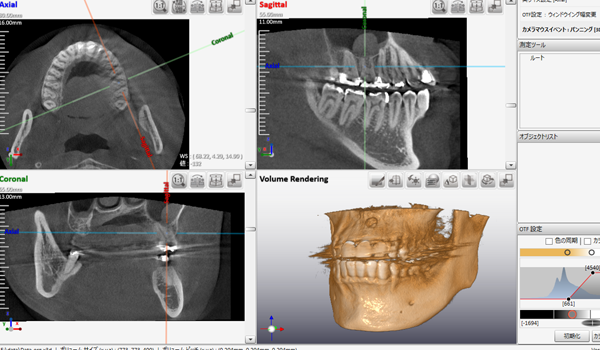

コンピュータを駆使しデータ処理と画像の再構成を行うことで、断層写真を得ることができる装置です。

歯科用CTとは、歯科に特化したCT装置で、コーンビームCTとも言われています。

歯科用CTとは、コーンビーム式のスキャンを行う事で、短時間のX線照射による、歪みの少ない繊細な画像を得ることができます。

インプラント治療

しかし歯周病などの原因で骨が少ないケースがあります。骨の量を確認するためにCTは必要となります。

下の奥歯にインプラント処置をする場合、下歯槽神経などの重要な神経を傷つけないために下歯槽管の位置を確認するために使用します。